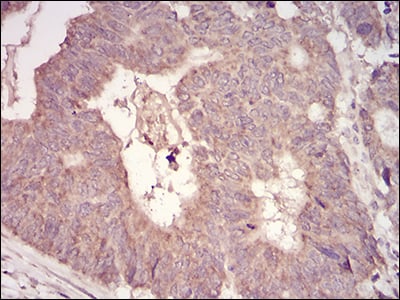

IHC (Immunohistochemistry)

(Immunohistochemical analysis of paraffin-embedded human rectum cancer tissues using anti-MuRF1 antibody. Counter stained with hematoxylin.)